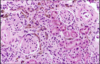

What is this?

Albumin

What is this?

What is this?

What dz?

inflammatory process w/associated immunologic response that leads to renal glomeruli damage.

*allows blood cell passage*

NephrITIC** syndrome**